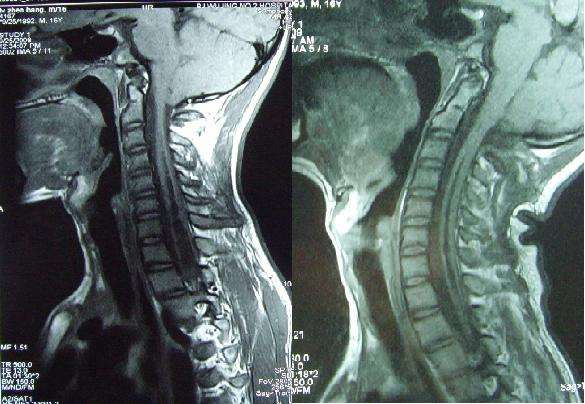

病例一:张某,男,16岁,枕部疼痛,双侧上肢麻木2年,双上肢无力,肌肉萎缩1年。

术前可见脊髓空洞;术后 可见脊髓空洞缩小